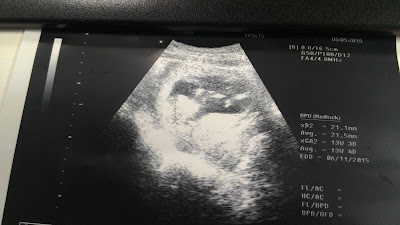

Okie dokie da update pasal scan on 18 weeks, i just snapped scan image ms 12 weeks aritu [3 mo], ms tu baby pon da grak2 active cuma xdpt rs lg. skrg dpt rase sket2. nnt dpt rs byk lah lagii...

Ade checkup aritu sbnarnye da exceed date coz suppose the check update when i was in Kelantan. so dtg2 check up first time hubby teman coz dia pon cuti :) then bile nurse panggil ckp, suppose xbole dtg jumaat [date yg suppose dtg is hari rabu, lewat 2 hari] sbb xde org nk check ke ape tah. tp seb bek lpas jugak sbb klo xmsk juge coz next week nye nk balik kdah pulak. then doc scan perot. uri kt atas, means OK, cuma bile scan deliver date is 3/11 which is seminggu awl dr date yg di calculate manual based on my period cycle and doc tu nk makesure lg, so kene dtg lagi dlm ms 2 weeks time.

Annnddddd latest check up haritu which is 16th June, doc scan lagilah perot sbb aritu doc sruh dtg kan. and teringat lah ape yg di baca dlm babycenter tu, 18 weeks ptotnye da nampak baby is a girl or boy. errmmm...anak first mmg accept saje girl or boy tp aku lebih nk ke boy sbb anak sulong klo perempuan cm susah cket. mcm my mom, me myself pon anak sulong jugak. so better boy for anak sulong. depends on masing2 lah kan. and 18 weeks onwards gak ptotnye bole rse da baby movement, cume stgh org yg br prego mayb xdpt rs sgt or confuse dgn ape yg dirasekan. few weeks lagi mayb bole rs dgn clear kot baby kicking! tazabarrrrrrr.LoL.